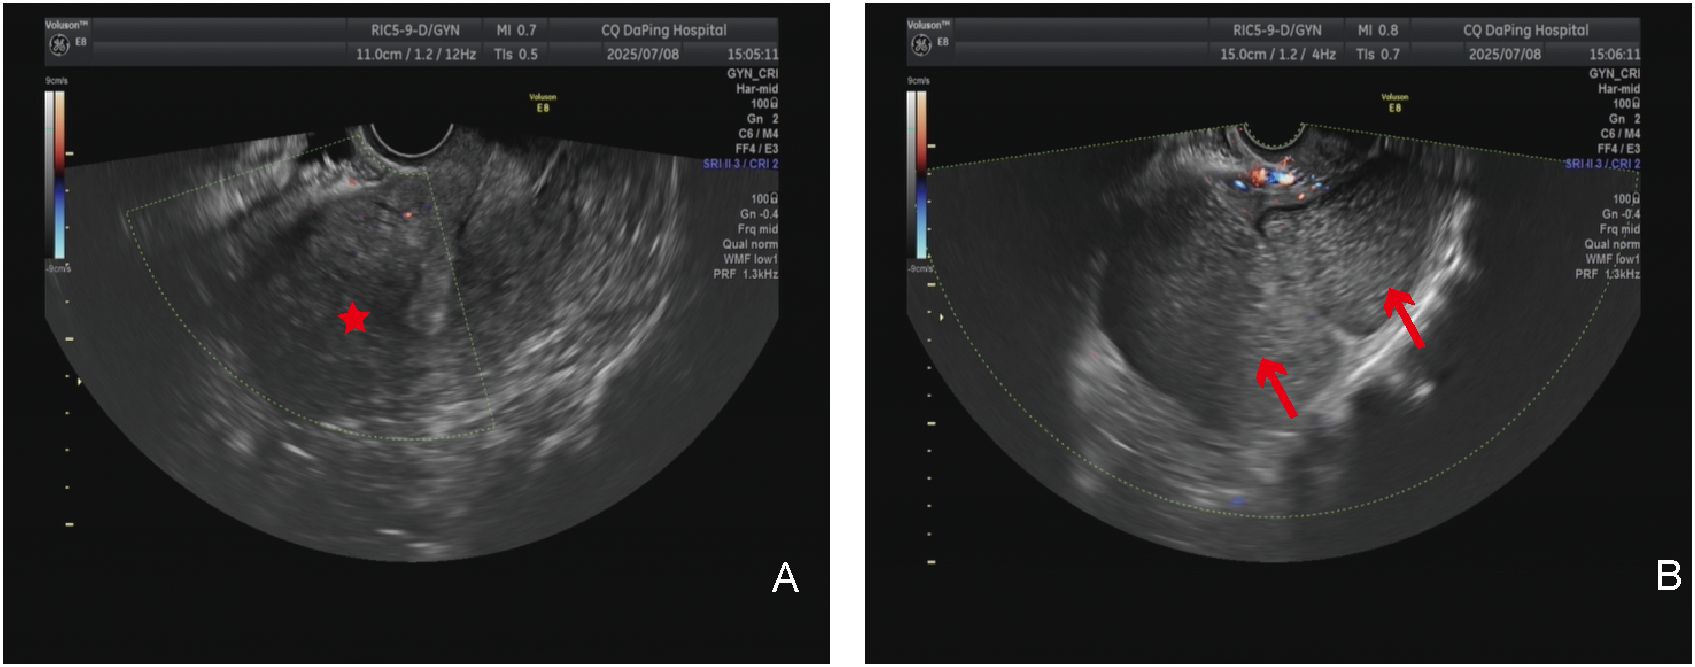

The patient is a 51-year-old woman with regular menstruation. She reported that a pelvic cystic mass, approximately 8 cm in size, was detected during a physical examination 7 years ago. Previous medical reports from prior visits are missing, with specific details unknown, and she did not receive regular follow-up visits (Figure 1). She came to our hospital for a physical examination 3 days ago; on examination, the uterus was enlarged to the size of an 8-week pregnancy, and a 14-cm cystic mass was palpable adjacent to the uterus, with good mobility, close relation to the uterus, and no tenderness or discomfort. Gynecological ultrasound in the patient showed the following findings: (1) The anterior myometrium of the uterus presented with coarsened and enhanced echoes, with a heterogeneous echo area measuring approximately 4.9 × 4.8 cm, featuring ill-defined borders and no capsule noted. (2) A 14.1 × 9.7 cm cystic anechoic lesion was observed in the left adnexal region of the uterus, which was thick-walled with poor sound transmission and showed deposition of medium-echoic spots. This anechoic space-occupying lesion was closely related to the uterus. Ultrasound-based diagnostic considerations were as follows: (1) uterine adenomyoma and (2) cystic space-occupying lesion in the left adnexal region (O-RADS category: 3) (Figures 2A, B). Routine auxiliary examinations showed no abnormalities. Since the onset of the condition, the patient has had no discomforts such as increased menstrual flow, abdominal pain, abdominal distension, frequent urination, or constipation.

Panel A shows an ultrasound image with a red star indicating a specific area of interest. Panel B features another ultrasound image with two red arrows pointing to distinct regions of interest. Both images display clinical annotations and technical details at the top.

Figure 2. Imaging examination: (A) Transvaginal ultrasound examination; the red asterisk indicates the uterus. (B) Transvaginal ultrasound examination; the red arrow shows the giant cyst of the uterus.